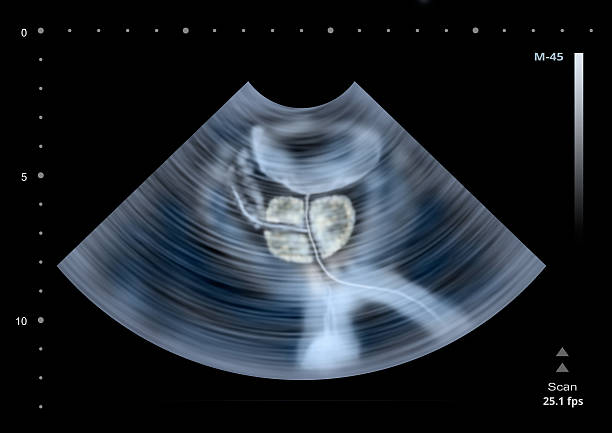

전립선비대증의 정확한 원인은 알려지지 않았으나, 나이와 성호르몬의 변화, 유전적 요인 등이 영향을 미친다는 것이 알려져 있습니다. 진단은 일반적으로 증상 및 신체검사와 방광내시경, 요로피부종영상술(IVP), 전립선 생검 등의 검사를 통해 이루어집니다.

이 방법은 고주파 음파를 이용하여 전립선 조직을 소멸시키는 것입니다. 이 방법은 고효율이며 합병증이 적은 것으로 알려져 있습니다. 초음파 치료는 일반적으로 중등도의 전립선비대증 증상을 가진 환자에게 시행되며, 침습적인 방법에 비해 회복 기간이 짧은 장점이 있습니다.